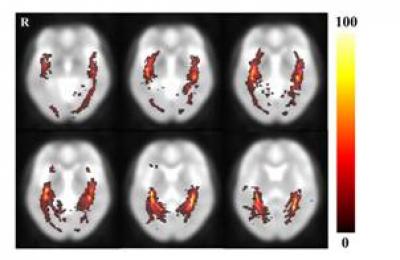

The optic radiation is a dense fiber tract that emerges from the lateral geniculate nucleus and continues to the occipital visual cortex. Especially, the optic radiation is an important fiber structure that conveys visual information from the lateral geniculate nucleus to the primary visual cortex in the occipital lobe. Current studies have focused on the anatomical characteristics of optic radiation fiber tracts in individual brains and on comparisons of the anatomical characteristics of the optic radiation fiber tracts between patient and control groups. Therefore, no diffusion tensor tractography studies of the volumetric information of optic radiation have been conducted without individual brain structure variation. To attain the volumetric information of the optic radiation in normal human brains, Dr. Cheol-Pyo Hong and coworkers from Korea Research Institute of Standards and Science (KRISS) performed diffusion tensor imaging examination in 13 healthy volunteers. Their results showed that the measured optic radiation fiber tract volume was a range of about 0.16% and that the fractional anisotropy value was about 0.53. Moreover, the optic radiation probability fiber pathway that was determined with diffusion tensor tractography-based group mapping was able to detect the location relatively accurately. The methods and results from Dr. Cheol-Pyo Hong and coworkers are helpful in the study of optic radiation fiber tract information, which has been reported in the Neural Regeneration Research (Vol. 9, No. 3, 2014).